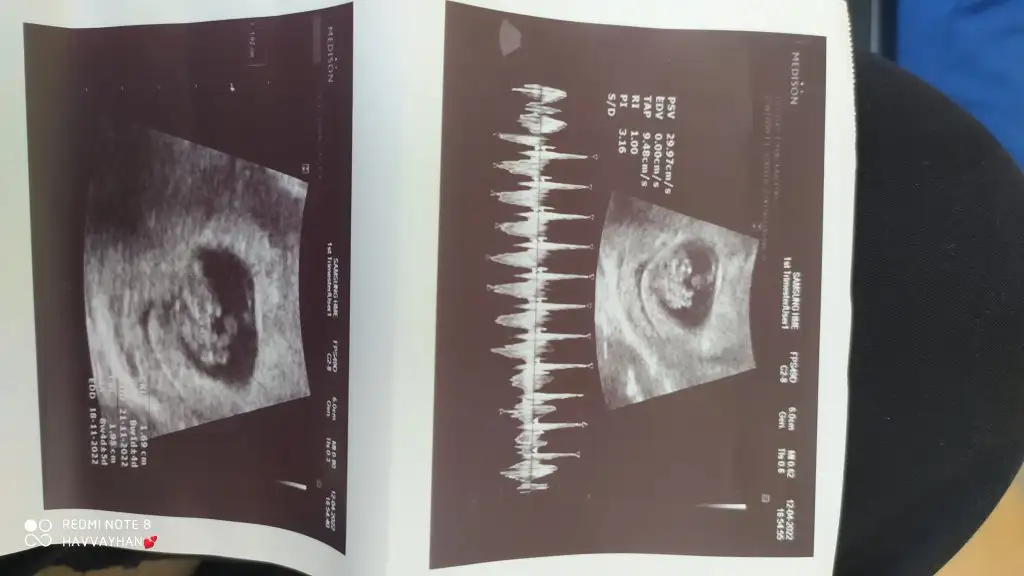

Hanımlar merhaba. 11 haftalık hamileyim. Erken olduğunu bilmeme rağmen doktora cinsiyeti ne olabilir diye sorduğumda kesin olmamakla birlikte bir olasılıktan bahsetti. Ramzi teorisi de denilen durum kısaca plasentanın duruşuna göre bebeğin cinsiyetini belirlemede yardımcı olduğunu söyledi. Benim plasentamın sağ arkada olmasından dolayı %60 erkek olabileceğini söyledi. Böyle bir ihtimal var mı gerçekten? Cinsiyet tahmini bu şekilde tutan oldu mu?